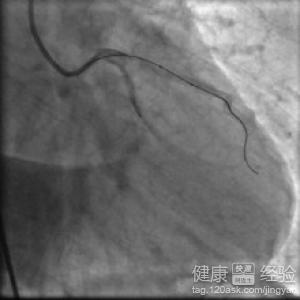

3另外,患有心動過緩心悸的患者,由於心跳比較的緩慢一些的,嚴重的是不能夠雞翅一個正常的生活的,所以需要安裝起搏器的,建議患者有心動過緩心悸的症狀的,一定要盡快看醫生。